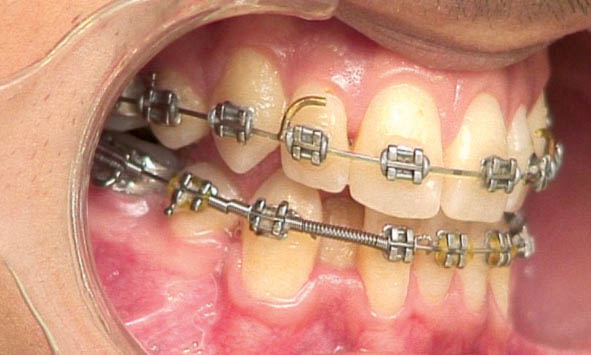

به جای استفاده از فنر باز که باعث زخم شدن گونه بیمار میشود میتوانید نوع بسته فنر را به اندازه فضای دو براکت ببرید سپس یک میلیمتر از هر طرف آن را بگیرید و بکشید (شکل 186-1) نهایتاً در دو سر آن فنر closed و در وسط فنر open دارید. بعد از درگیر کردن این فنر و باز شدن فضا حتی اگر فنر بچرخد دیگر لبههای تیز ندارد لذا باعث آزردگی لب و گونه بیمار نمیشود.

ضمناً دو قطعه یک میلیمتری هم جدا کنید و در پشت براکت کانین بگذارید (شکل 187-1) تا بعد از دو ماه که نیروی فنر اصلی کاهش یافت بتوانید با اینها، فنر اصلی را فعال کنید (شکل 188-1) تا مجبور به صرف وقت زیاد برای تعویض کل مجموعه نشوید.

روی براكت سانترال و کانین را با سیم لیگاچور میبندیم تا چرخش ایجاد نشود (شکل 189-1) چون سیم لیگاچور، آرچ وایر را روی براكت محكمتر از اورینگ نگه میدارد.

شکل 186-1: کشیدن فنرکلوز استیل باعث باز شدن فنر میشود.

شکل 187-1: پشت کانین دو قطعه از فنر کلوز به طول 1mm برای فعال کردن در ماههای بعدی قرار دهید.

شکل 188-1: اضافه کردن قطعه فنر کمکی برای فعال کردن فنر در ناحیه لترال

شکل 189-1: وایر لیگاچور کردن دندانهای پایه فنر برای جلوگیری از چرخش آنها